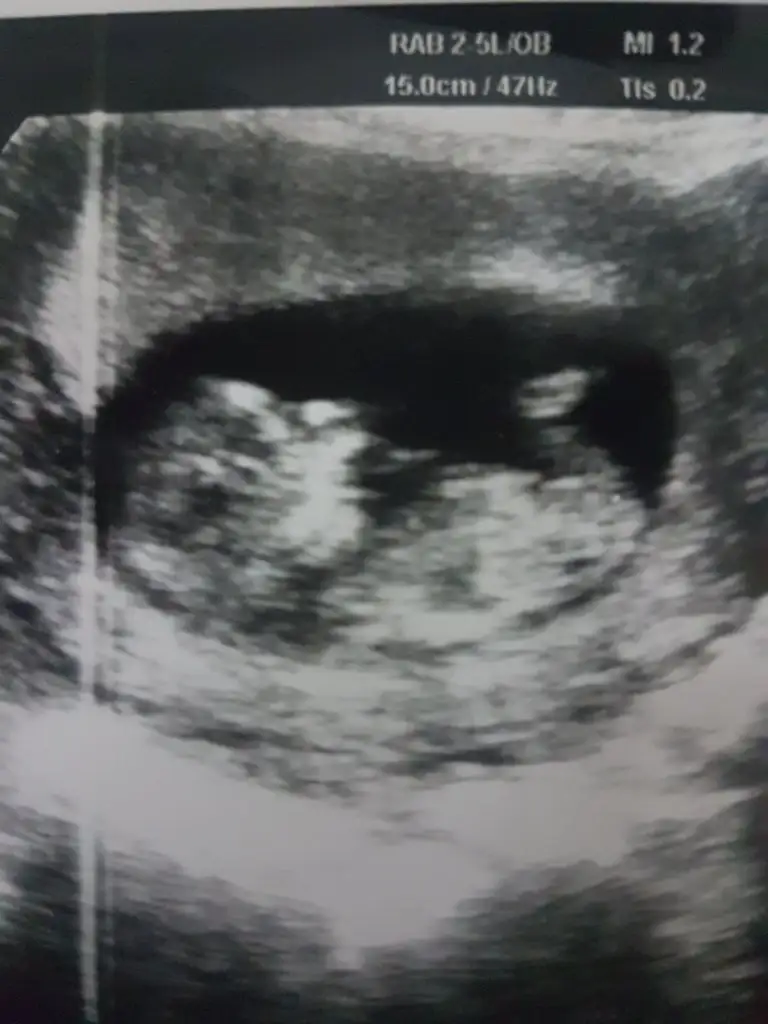

9 haftalik burda

Eki Görüntüle 2935643